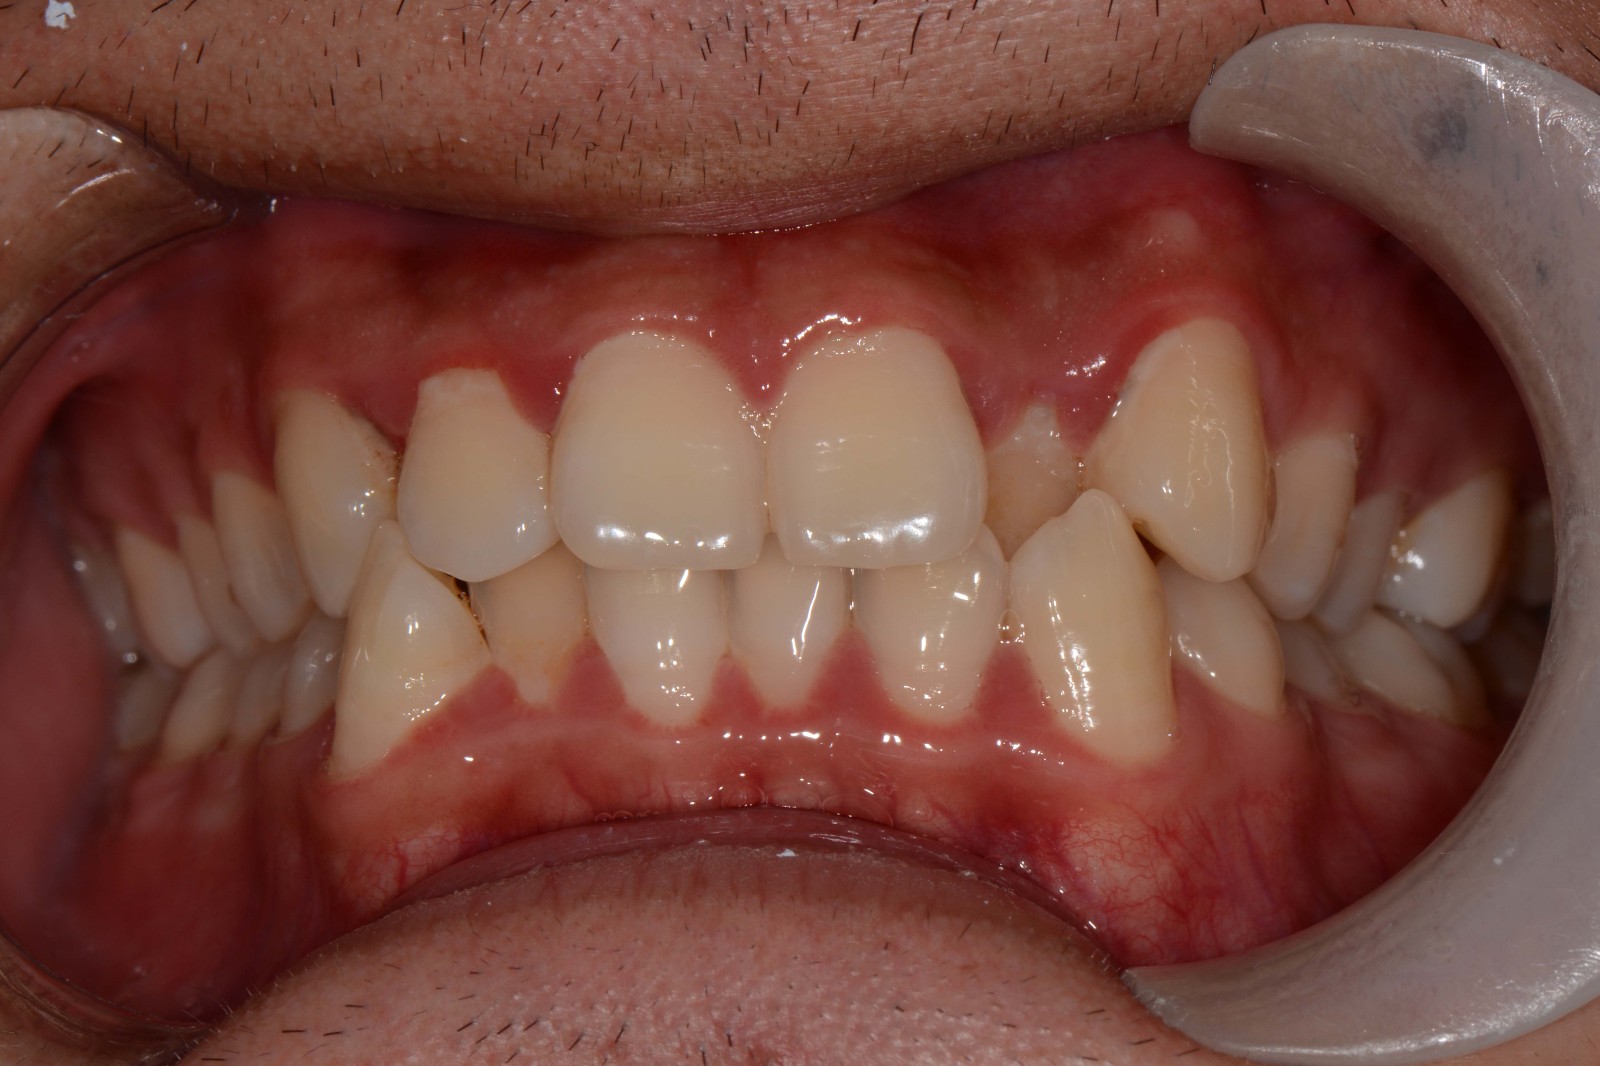

治疗方案:不拔牙矫治,适量扩弓,唇倾前牙排齐整平上下颌牙列,视情况做IPR,调整覆合覆盖,精调,保持,定期复查。

矫治后: